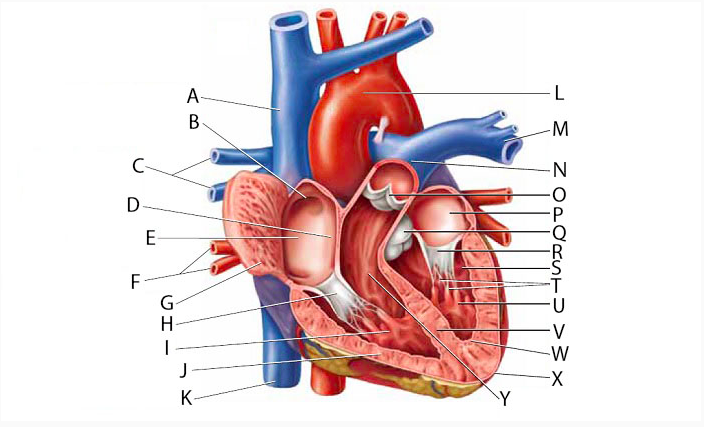

Aortic Arch

Aortic Valve (=left semilunar)

Apex (of the heart)

Ascending/descending aorta

Brachiocephalic vein

Chordae tendineae

Coronary sinus

Endocardium

Epicardium

Left atrioventricular (=bicuspid, =mitral) valve

Left/right atrium

Left/right auricle

left/right ventricle

Myocardium

Papillary muscles

Pectinate muscles

Pulmonary trunk

Pulmonary valve (=right semilunar)

Right atrioventricular (=tricuspid) valve

Superior/inferior vena cava